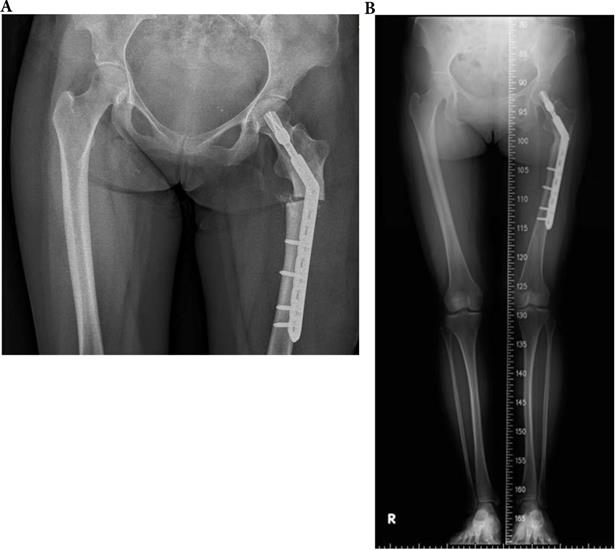

Figure 3

A 33-year-old type 4 OI female suffered a left shaft femur fracture with plate fixation treatment in December 2015, resulting in union. (a) Just finished operation in December 2015 (b) Follow up in August 2016.

Int J Med Sci Image

Influence of treatment on healing rate

In OI type 4, 2 of 5 (40.0%) fractures resulted in non-union. All two patients with type 4 OI who were conservatively treated with OI had shaft fractures resulting in non-unions. Three other patients with type 4 were surgically treated for shaft fractures. All resulted in union (2 IN, 1 PF) (Figures 3, 4, 5). In patients with OI with type 1 OI, 1 of 4 (25.0%) fractures resulted in non-union (Figure 6), for type 3, 1 of 6 (16.7%) fractures resulted in non-union (Figure 7).